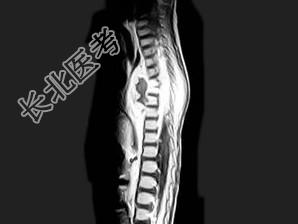

- 单项选择题男,8岁, 咳嗽、咳脓痰,背部肿痛。结合图像, 最可能的诊断是 ( )

E、脊椎结核